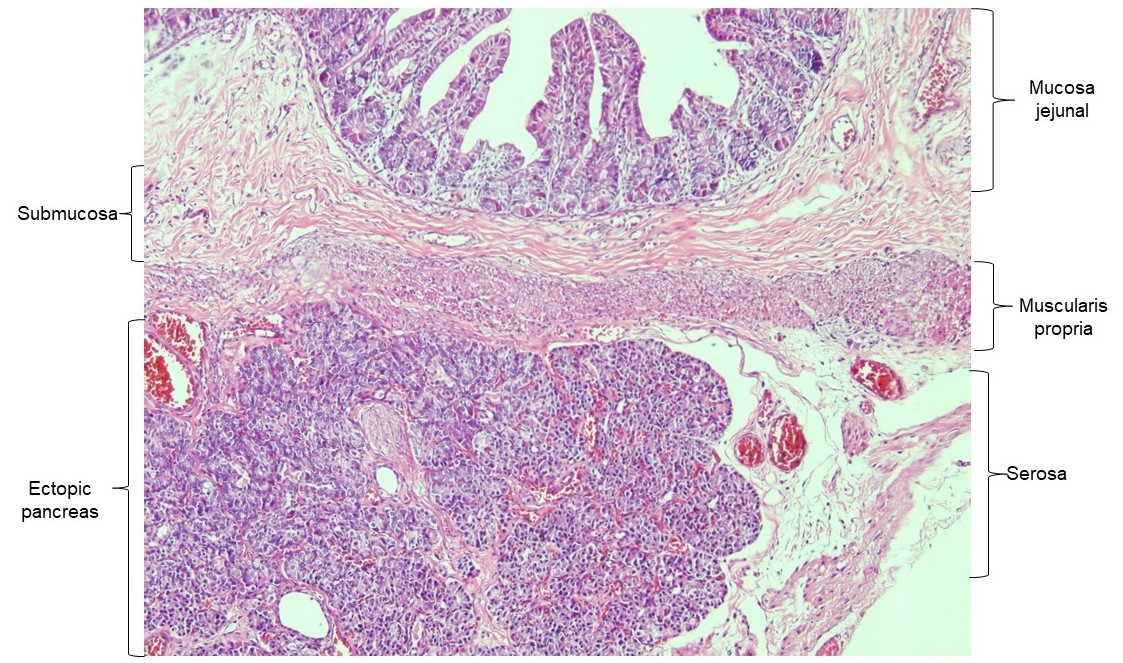

The histology report described a light brown color nodule that was 0.3 cm in diameter. It was formed by ectopic pancreatic tissue located in the jejunal serosa (Fig. 2).

EP is found in the submucosal layer of the intestine in 54% of cases, 23% is found in submucosa and muscularis propria, 8% of cases only in the muscularis propria, 11% in subserosa, and only 4% compromises the whole intestinal wall. [10] Our case was limited to serosa. In 2019 Hamada et al. [11] described 5 cases of neonatal jejunal EP of which 3 were females and 3 presented with extramural EP, as in our case.

Heinrich´s histologically classified EP in 4 types. This classification was modified by Fuentes in 1973. Type 1 is the most frequent according to the literature. [2], [11] All the tissues that normally form the pancreas were found in our sample, therefore it was histologically classified as type 1.

Figure 2

Histopathology of the resected jejunum showing pancreatic tissue in the serosa.